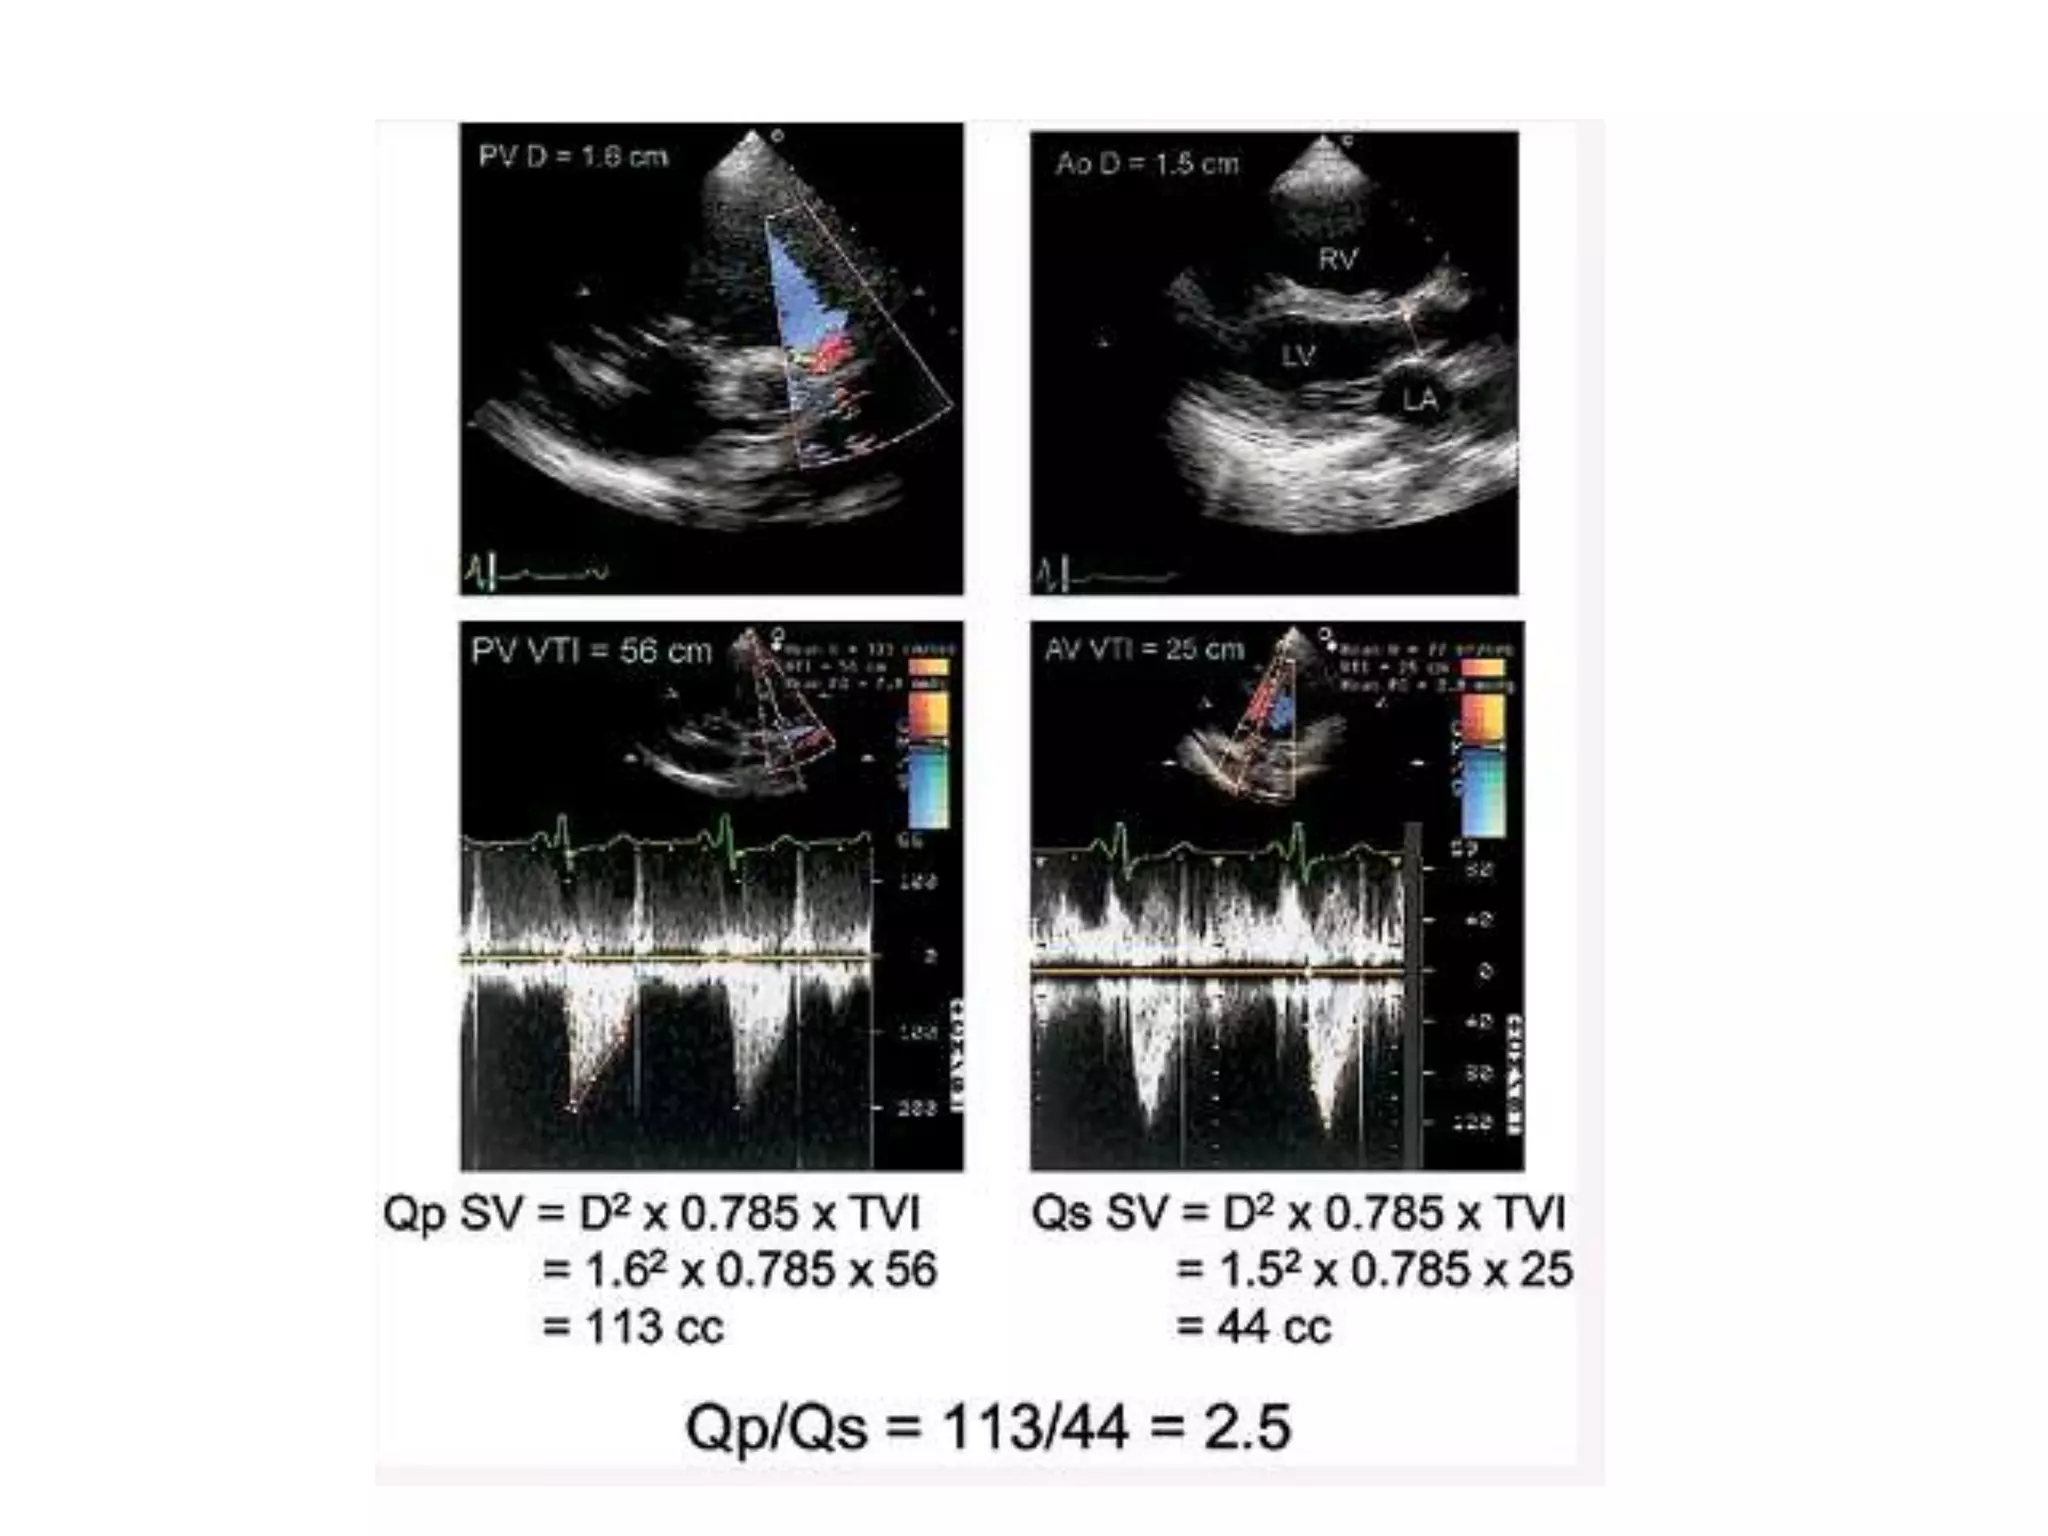

Measurement of ASD size

• Maximal ASD

diameter must be

measured at the end

of ventricular systole

• Atleast two

orthogonal views

• SBP = Max in TEE + 4

to 6mm